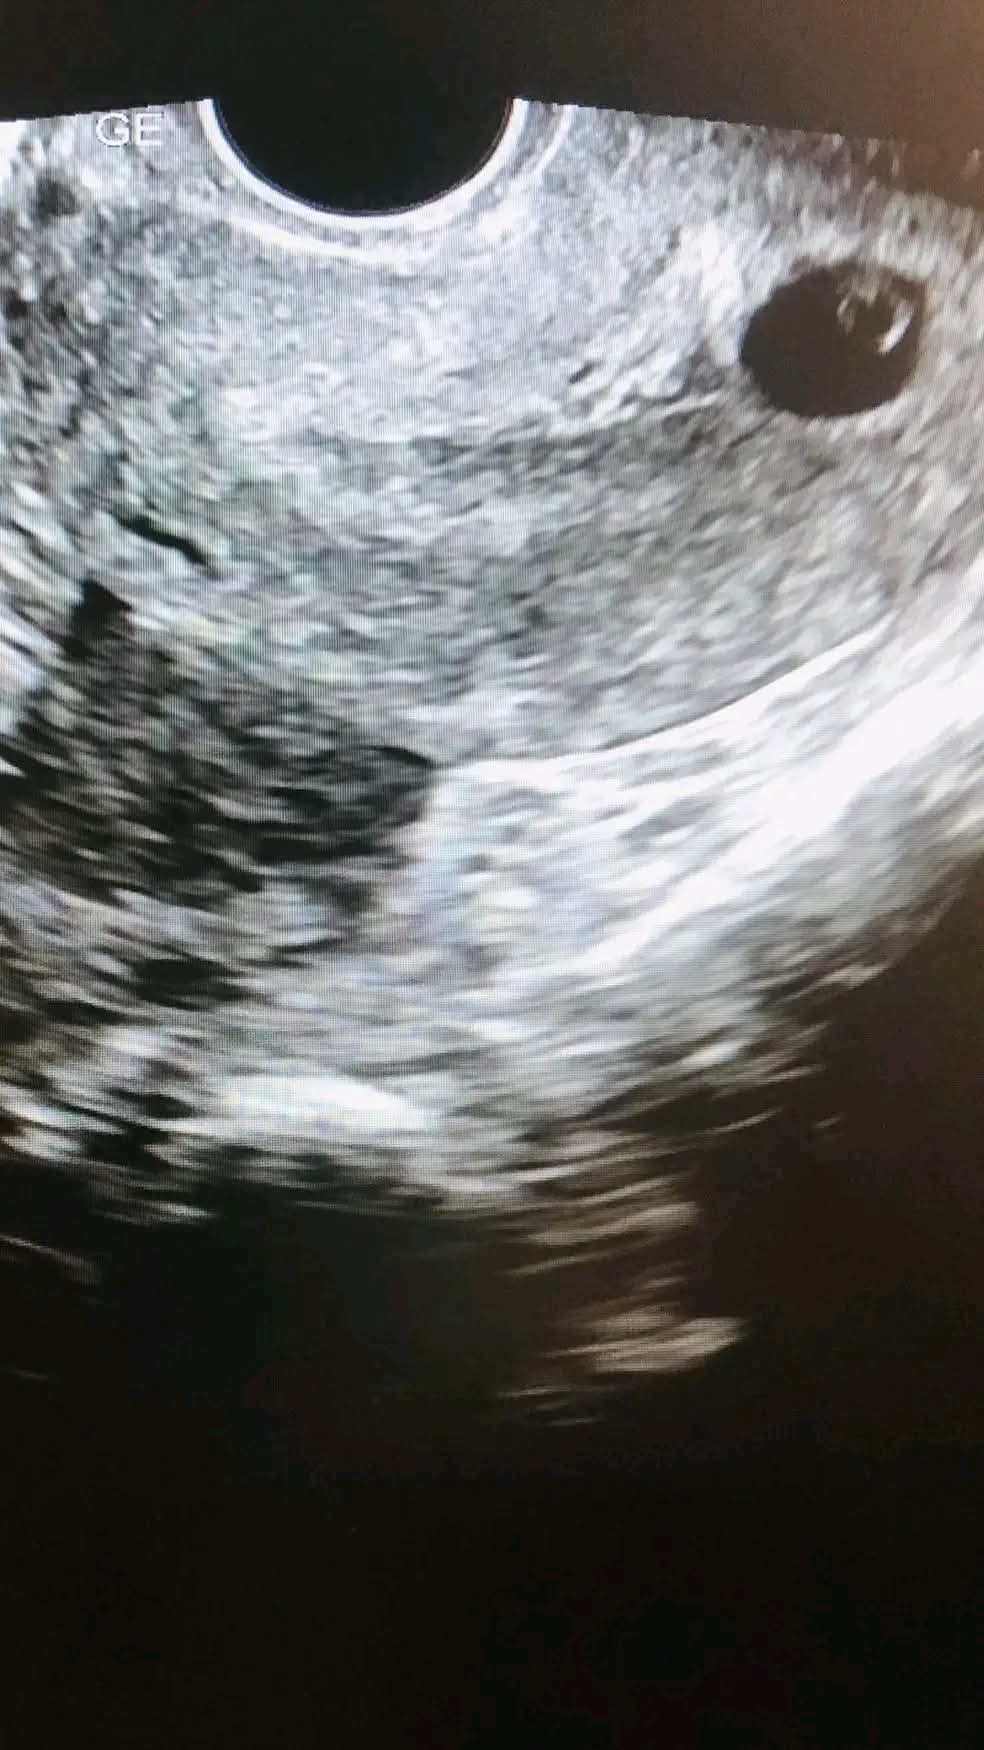

சரி ஸ்கேன் செய்து பார்க்கலாம் தண்ணீர் குடியுங்கள் என்றேன் , நான் நோன்பு இருக்கிறேன் தண்ணீர்குடிக்க முடியாது என்று மறுத்து விட்டார் கட்டாயம் ஸ்கேன் எடுக்கவேண்டும் என்றால் இரவு நோன்பு திறந்தவுடன் வருகிறோம் என்றார்கள் ##இந்த மயக்கமான நிலையில் வீட்டுக்கு செல்வது சரியல்ல என்று தண்ணீர் குடிக்காமல் Trans vaginal scan செய்து பார்பது நல்லது என்று அவர்களை சம்மதிக்க வைத்தேன்

நான் நினைத்தது சரியாகதான் இருந்தது,ஆம் சுபேதா கர்ப்பபையில் 5 வார குழந்தையின் கரு & இதய துடிப்புடன் இருந்ததை அவர்களிடம் காண்பித்த பொழுது இருவரும் நம்பவில்லை